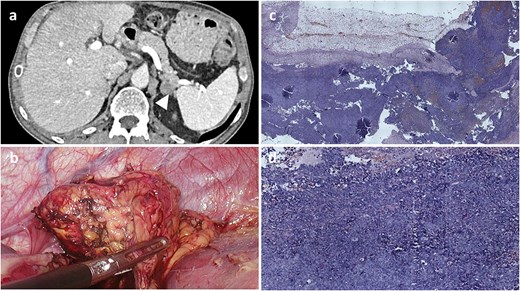

In June 2022, 13 months after surgery, abdominal CT detected a 20.5-mm mass in the left adrenal gland extending toward the pancreatic tail (Fig. 4). Following multidisciplinary team evaluation, the patient underwent a laparoscopic left adrenalectomy, lasting 45 min, with an estimated blood loss of 80 mL. The tumor was completely resected, and the patient recovered without postoperative complications.

Radiological, intraoperative, and histopathological findings of adrenal metastasis. (a) Computed tomography revealing a 20.5-mm mass in the left adrenal gland extending toward the pancreatic tail. (b) Intraoperative view of the adrenal mass. (c and d) Microscopic examination (H&E) showing malignant pigmented melanoma within adrenal gland tissue.

Microscopic examination revealed a tumor composed of epithelioid cells with heterotypic nuclei, nuclear grooves, folding nuclei, intranuclear inclusions, and multinucleation (Fig. 3c). Immunohistochemical staining was negative for inhibin, synaptophysin, cytokeratin-pan, and chromogranin A, while vimentin and melanocytic markers (S-100, human melanoma black-45) were strongly positive, confirming metastatic melanoma.